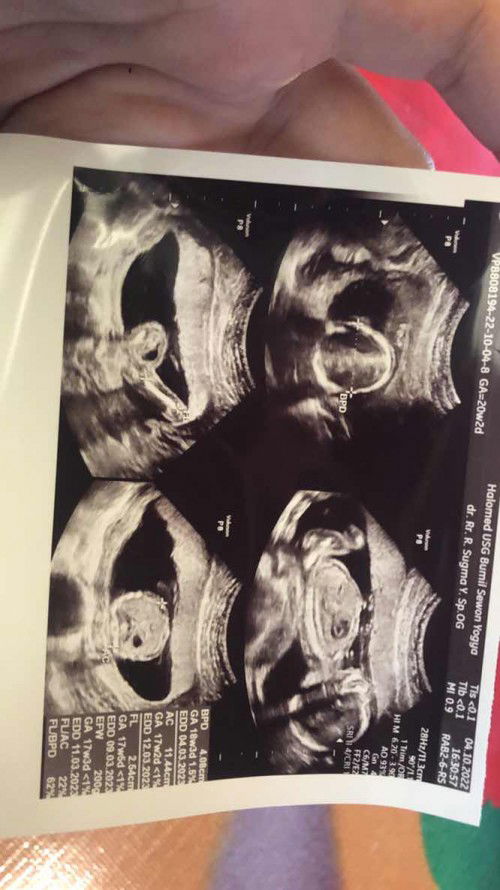

hai mom , mau tanya nih saya tadi usg tp kata dokternya beratnya masih kurang (sesuai usia kandungan saat ini) seharusnya 500gr, ini baru 200gr. solusinya buat nambah beratnya dong mom, misal harus mengonsumsi makanan/minuman apa aja atau suplemen apa?? terimakasih. #ingintahu #firstmom #pleasehelp #firstbaby